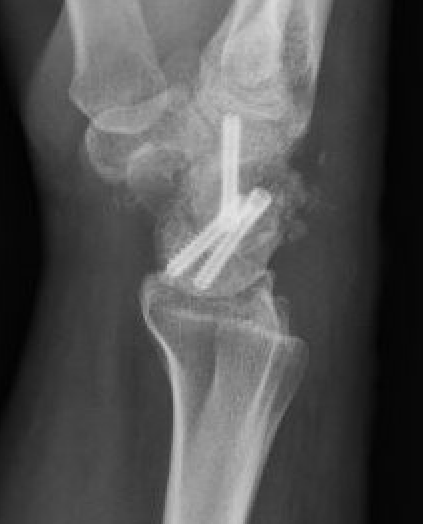

Vender Classification

| Stage I | Stage II | Stage III |

|---|---|---|

|

Radial styloid and distal scaphoid fragment

+ Proximal scaphoid and capitate | + capitate-lunate joint |

![]() |